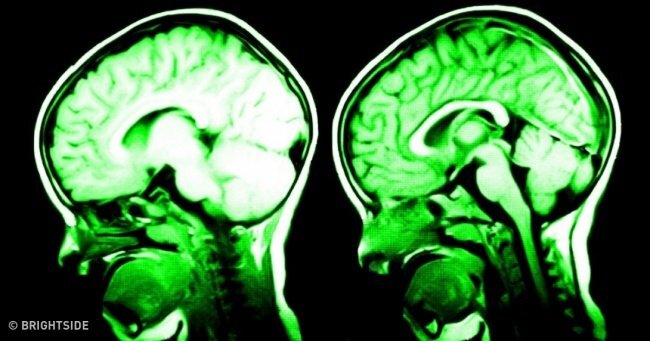

7 cách khiến não bộ hạnh phúc hơn

Tất nhiên, mỉm cười, ngủ trưa, chăm sóc con mèo, hít thở không khí trong lành, tiếp xúc nhiều hơn với ánh sáng mặt trời hay bất cứ hoạt động gì lành mạnh cũng đều làm cho não bộ của bạn hoạt động tốt hơn.